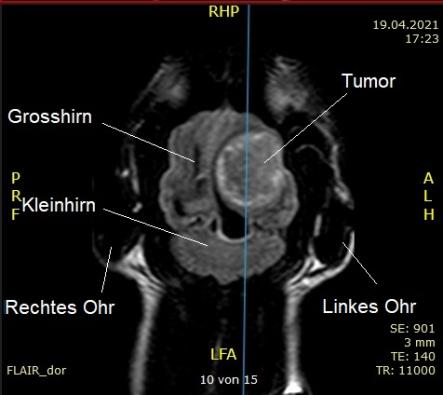

Nach einer kurzen Bedenkzeit entscheiden sich die Besitzer, nun weitere Abklärungen vorzunehmen, und Schnurrli wird an die neurologische Abteilung des Tierspitals Bern überwiesen. Eine Magnetresonanzuntersuchung des Kopfes zeigt, dass die Katze an einer grossen Krebsgeschwulst in der linken Hirnhälfte leidet, welche auf das Hirngewebe drückt. Am Wahrscheinlichsten handelt es sich dabei um einen (in der Regel gutartigen) Tumor der Hirnhaut, ein Meningeom.

Das Meningeom ist der häufigste primäre Hirntumor bei Katzen und Hunden. Es stellt eine Entartung der Meningen, also der das Hirn und das Rückenmark umhüllenden Hirnhäute, dar. Sie sind meistens gutartig (d.h. sie wachsen nicht in das umliegende Gewebe ein oder bilden Ableger) und wachsen langsam. Die Symptome entwickeln sich aufgrund des ständig zunehmenden Druckes auf das im Schädel eingeschlossene Hirn und können zu Beginn sehr subtil sein (Wesensänderung, vermehrtes Miauen oder Kratzen am Kopf). Zur Diagnose ist idealerweise ein MRT oder allenfalls ein CT notwendig; auf einem normalen Röntgenbild ist der Tumor meist nicht zu erkennen.

CT (Computer-Tomogramm) und MRT (Magnet-Resonanz-Tomogramm) sind moderne bildgebende Verfahren, bei welchen das Zielgebiet quasi in Scheiben geschnitten und so dreidimensional dargestellt werden kann (altgriechisch "tomo" = "Schnitt", "graphein" = "schreiben"). Beim CT wird dazu die altbewährte Röntgentechnik benutzt, indem die Röntgenröhre spiralig um das Zielgebiet geführt wird und dabei unzählige Aufnahmen macht. Eine CT-Aufnahme dauert kürzer als ein MRT, verursacht aber eine Belastung mit Röntgenstrahlen. Beim MRT wird ausgenutzt, dass die Atomkerne des Gewebes einen sogenannten Kernspin und damit ein kleines Magnetfeld besitzen. Mittels eines von aussen kurzfristig zusätzlich angelegten Magnetfeldes können aufgrund der folgenden Veränderungen der Ausrichtung der Atomkern-Magnetfelder im Zielgebiet Rückschlüsse auf den jeweiligen Gewebetyp gezogen werden. Die verschiedenen Gewebetypen werden als unterschiedliche Graustufen dargestellt. Bei beiden Untersuchungen muss der Patient absolut still liegen; entsprechend werden Tiere dazu in Vollnarkose versetzt.